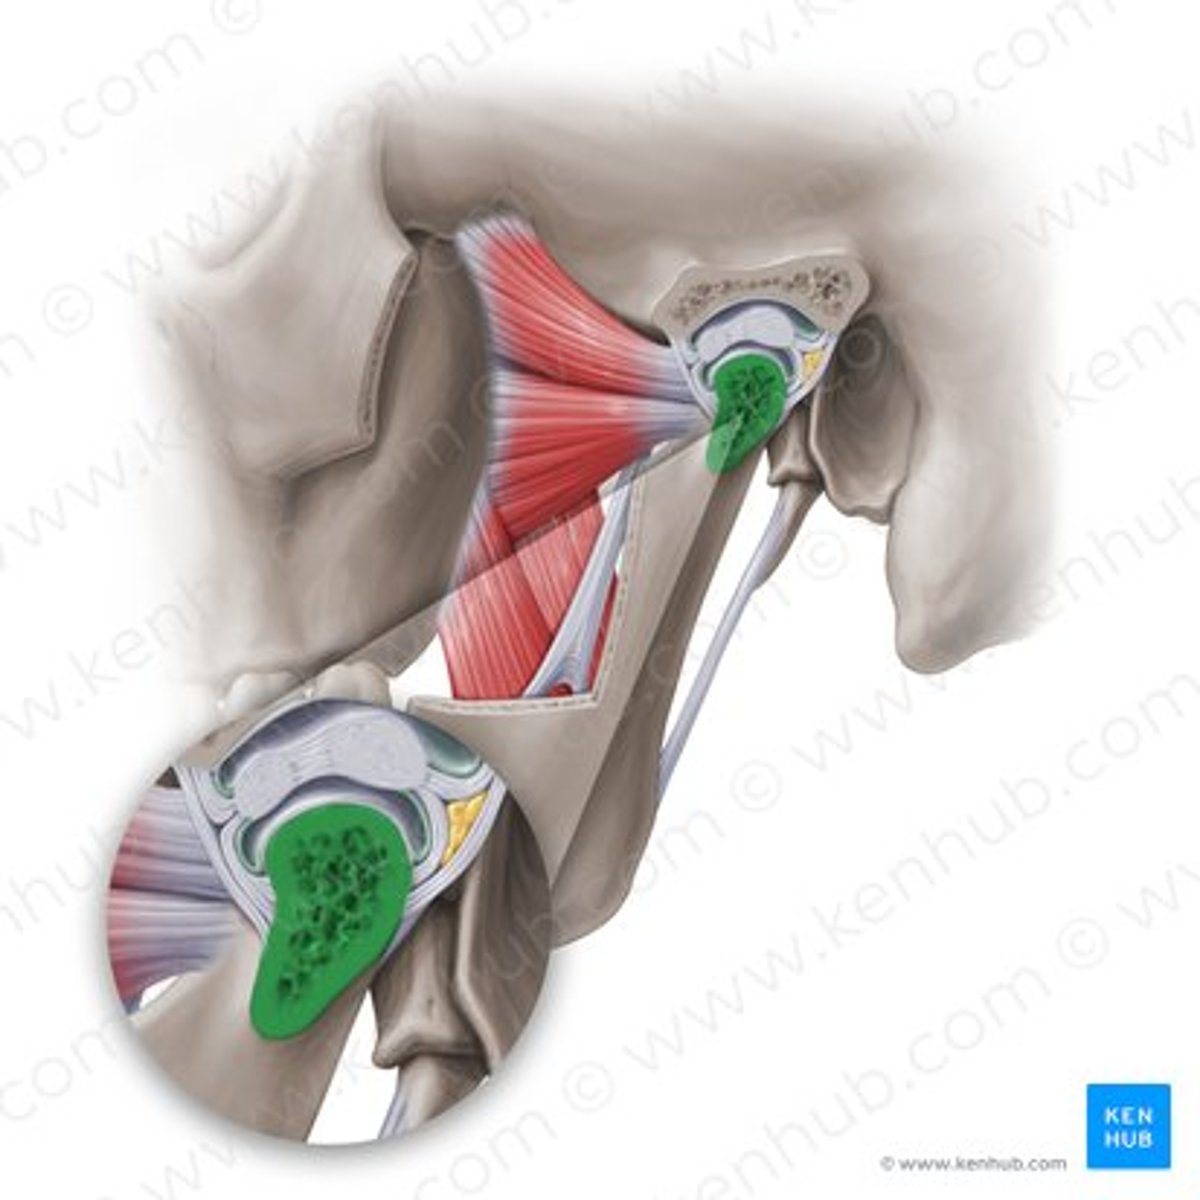

lateral pterygoid, superior part

lateral pterygoid, inferior part

articular tubercle

head of mandible

articular disk

joint capsule